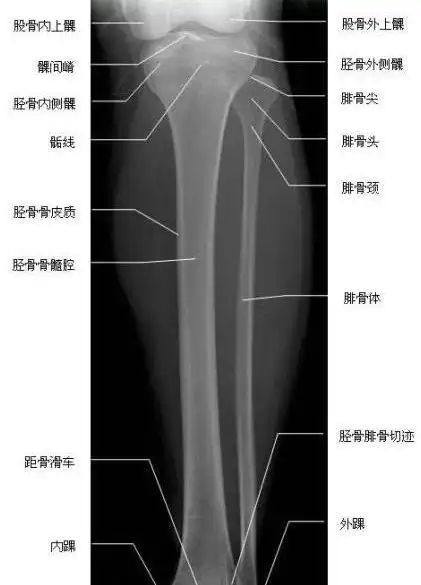

胫腓骨正位—x线